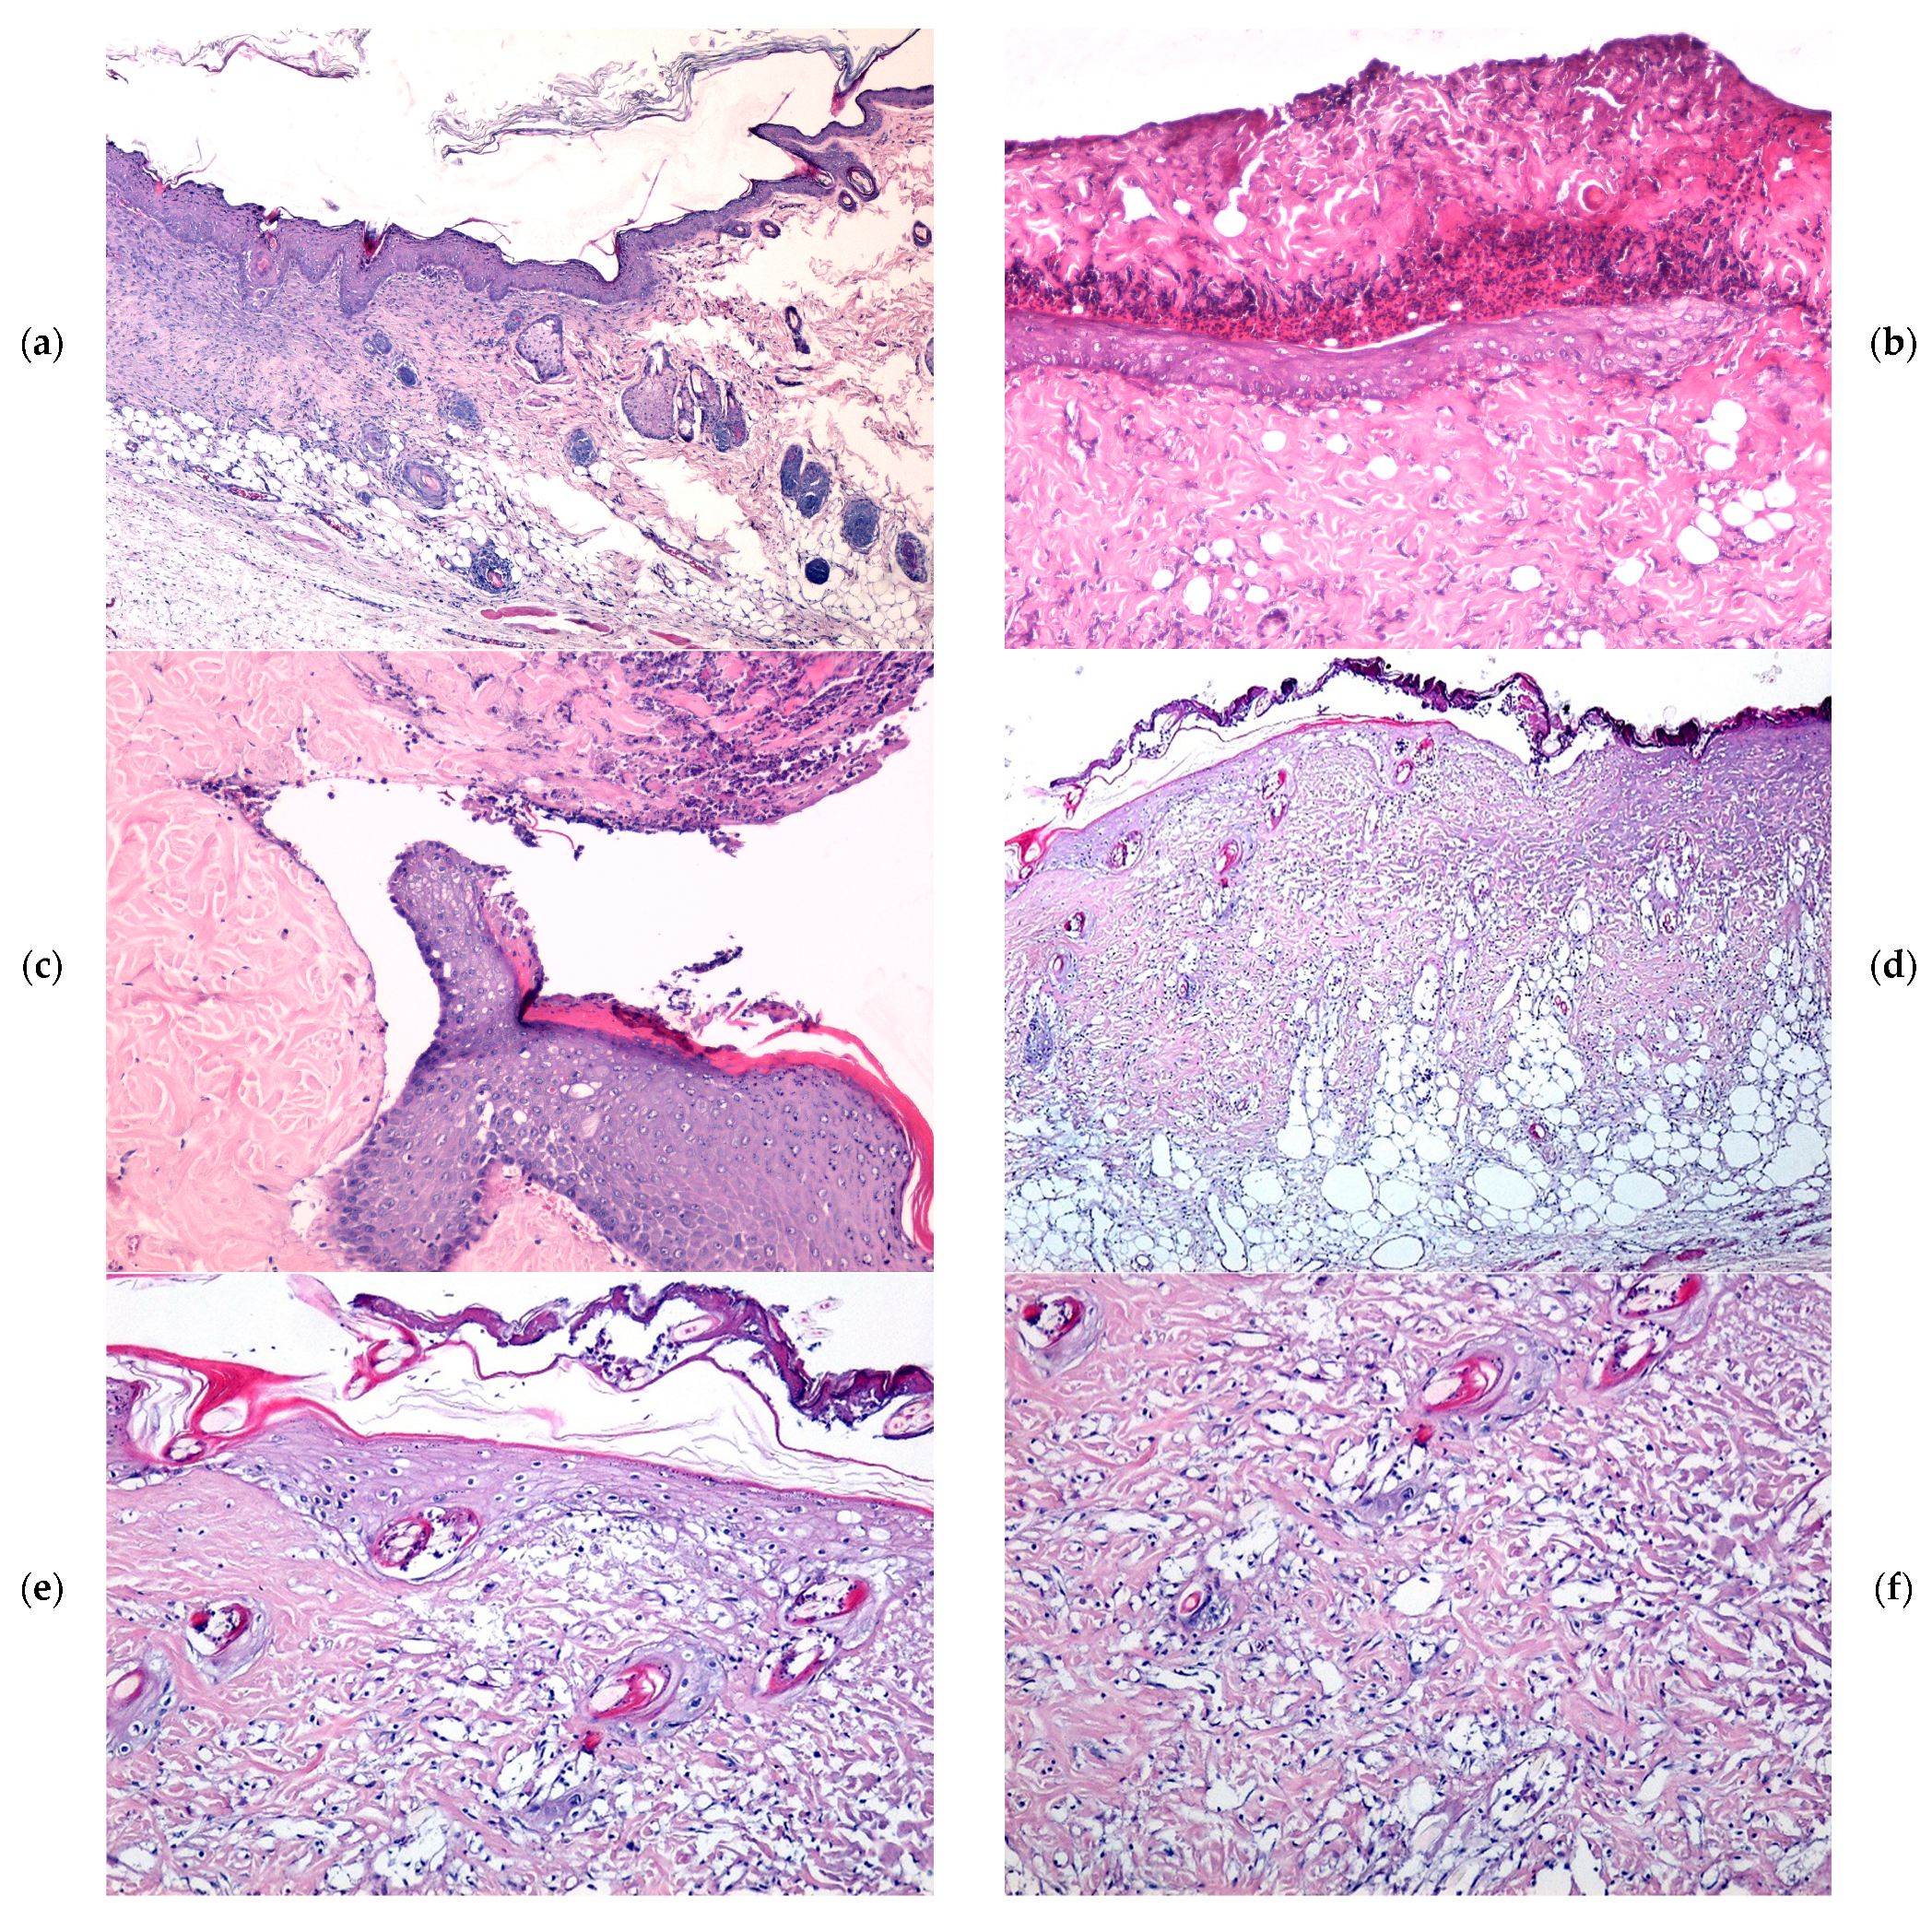

2.4. Microscopic Evaluation of Burn Wound Healing